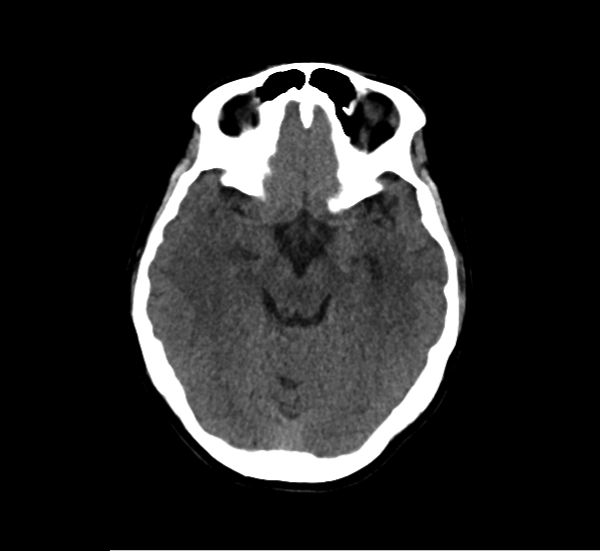

CT Brain Anatomy